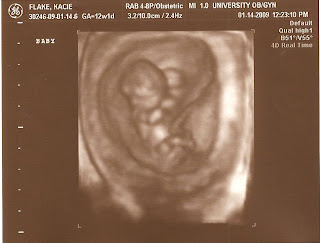

I stay really brave and they take me to to ultrasound room right away and give me an actual ultrasound to see whats up and finally, there is my baby wiggling all over on the screen (which is why the microphone thingy couldn't pick it up) So I get an early ultrasound and even got to take home 4D pictures already! Pretty nice perk for having my own heart stop beating.

Here's the proof that someone's in there!